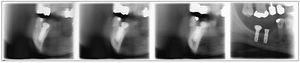

La opción de gran formato permite visualizar áreas más amplias. Por consiguiente, las imágenes longitudinales se utilizan cuando las radiografías intraorales no son suficientes por su pequeño formato (figs. 6 a 8).

Figura 6. Visualización deficiente del ápice radicular tras la apicectomía del diente 46.

Figura 7. Visualización completa y sin distorsiones con cortes estrechos longitudinales para el control de la apicectomía del diente 46.

Figura 8. Conductos radiculares obturados con una imagen radioopaca debida a una lesión poliposa basal del seno maxilar.